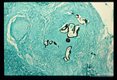

Gross and microscopic photos of human liver from Minnesota where about one half of the red foxes are infected.